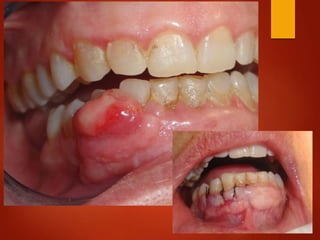

El documento es un registro médico odontológico que muestra las fechas de las visitas de un paciente al centro de salud El Raval, incluyendo exámenes y tratamientos realizados como la extracción de cálculos salivales en abril y mayo de 2012.